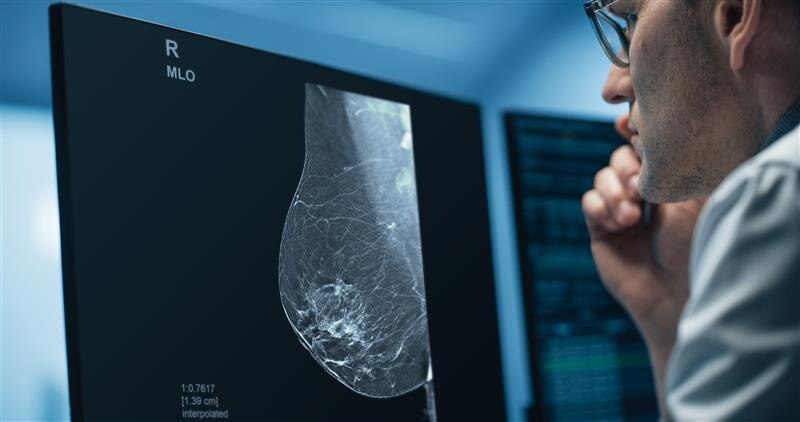

Pristina Recon DL

GEHC announced that it has received FDA Premarket Authorization for Pristina Recon DL.

Pristina Via

Download